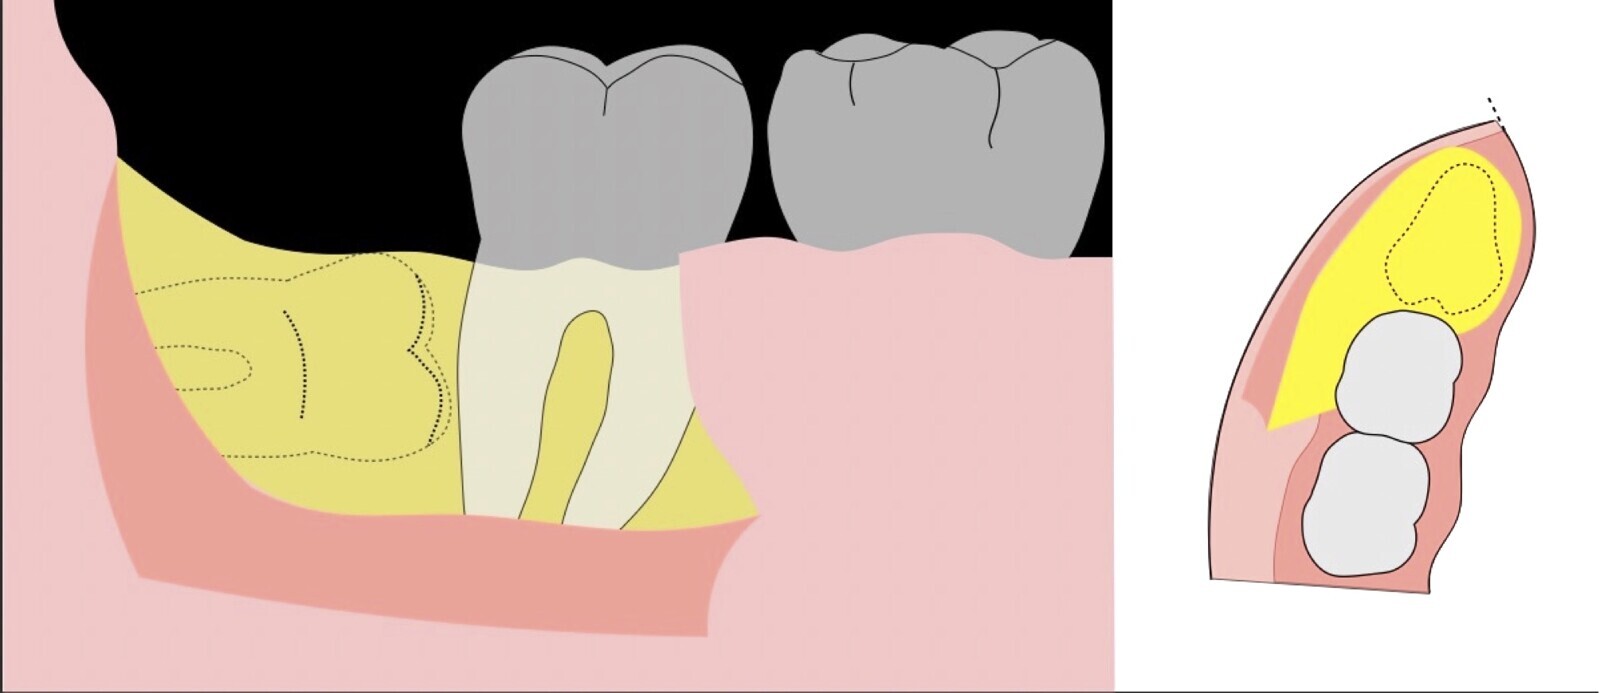

El procedimiento se inicia colocando anestesia troncular para bloqueo del nervio dentario inferior y sus ramas. Luego, se establecerá el diseño de acceso según la disposición de la molar a extraer. Para fines didácticos, se explicará cómo se realizaría la extracción de la molar de la Figura 1: se realiza una incisión horizontal a nivel de la zona retromolar hasta llegar a distal de la segunda molar, continuándose con una incisión intrasurcular hasta mesial de la segunda molar, finalizando con una incisión vertical a espesor total hasta llegar a la línea mucogingival (Figura 2).

Figura 2. Diseño de incisión para el acceso a la tercera molar.

Figura 3. Decolado a espesor total para el acceso a la tercera molar.

Figura 4. Demarcación de la zona de osteotomía con insertos de corte recto y/o angulado a nivel oclusal. Vista frontal (a). Vista oclusal (b).

Figura 5. Fractura y eliminación oclusal del fragmento óseo de la porción coronal oclusal.